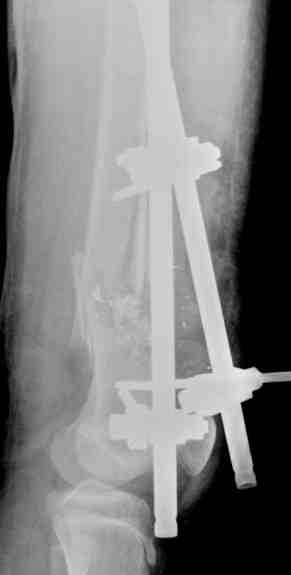

Выше представлены рентгенограммы открытого оскольчатого перелома нижней трети голени X-rays of Compound Comminuted # Distal/3 Lt Tibia

Операционные снимки перед и после наложения аппарата Илизарова In operation room before and after Ilizarov apparatus has been applied

Послеоперационные рентгенограммы Postoperative X-rays

В нижнем ряду представлены рентгенограммы после окончательной репозиции. And final reduction after Hexapod program has been finished